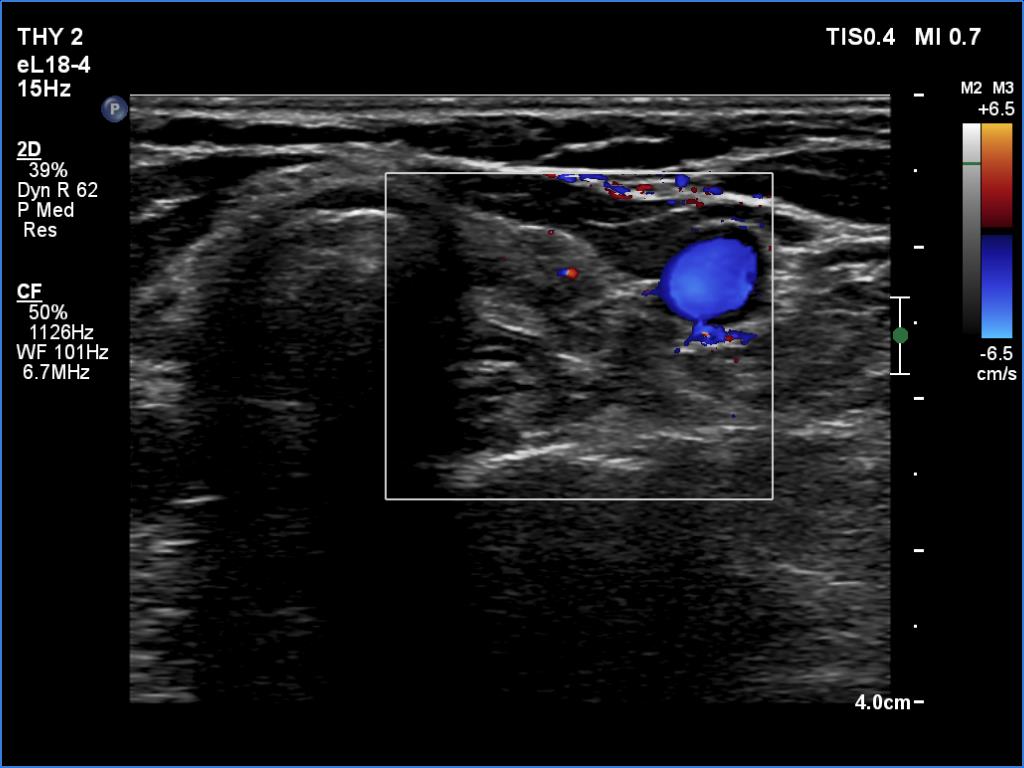

Left lobe, transverse scan, color Doppler mode. The vascularity is decreased.